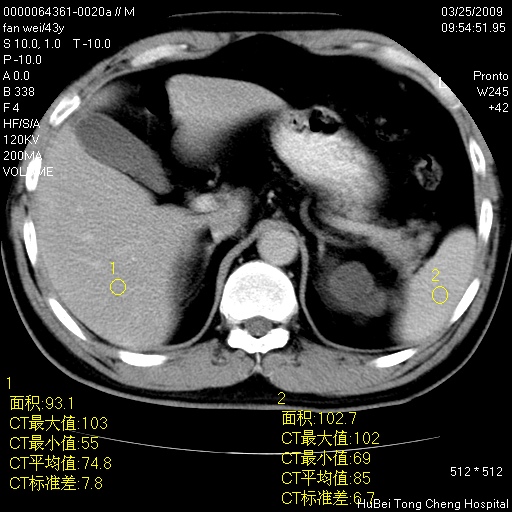

双肾ct轴位平扫+增强扫描(层厚10mm,螺距1.0,重建间隔10mm),图像如下:

多囊肾的影像诊断标准:有阳性家族史,年龄<30岁,单侧或双侧肾脏有两个肾囊肿;30~59岁,两侧肾脏各有两个肾囊肿;60岁以上,每侧肾脏有4个囊肿。敏感性和特异性达86%和80%。

此病例影像诊断符合,要结合家族史,腰痛、血尿、尿路感染史,有无高血压等综合判断,如无相应的临床症状,本身病变也无意义了(个人观点)

囊肿数得清,肾功能正常,考虑多发肾囊肿.另外,右肾后极突向肾周间隙的那个病灶是不是错构瘤,请楼主调窗看看.